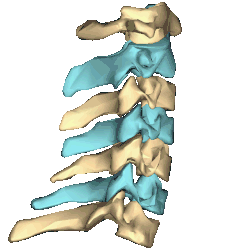

- Shape of cervical vertebrae (shown in blue and yellow). Animation.

- Cervical vertebrae, lateral view (shown in blue and yellow)